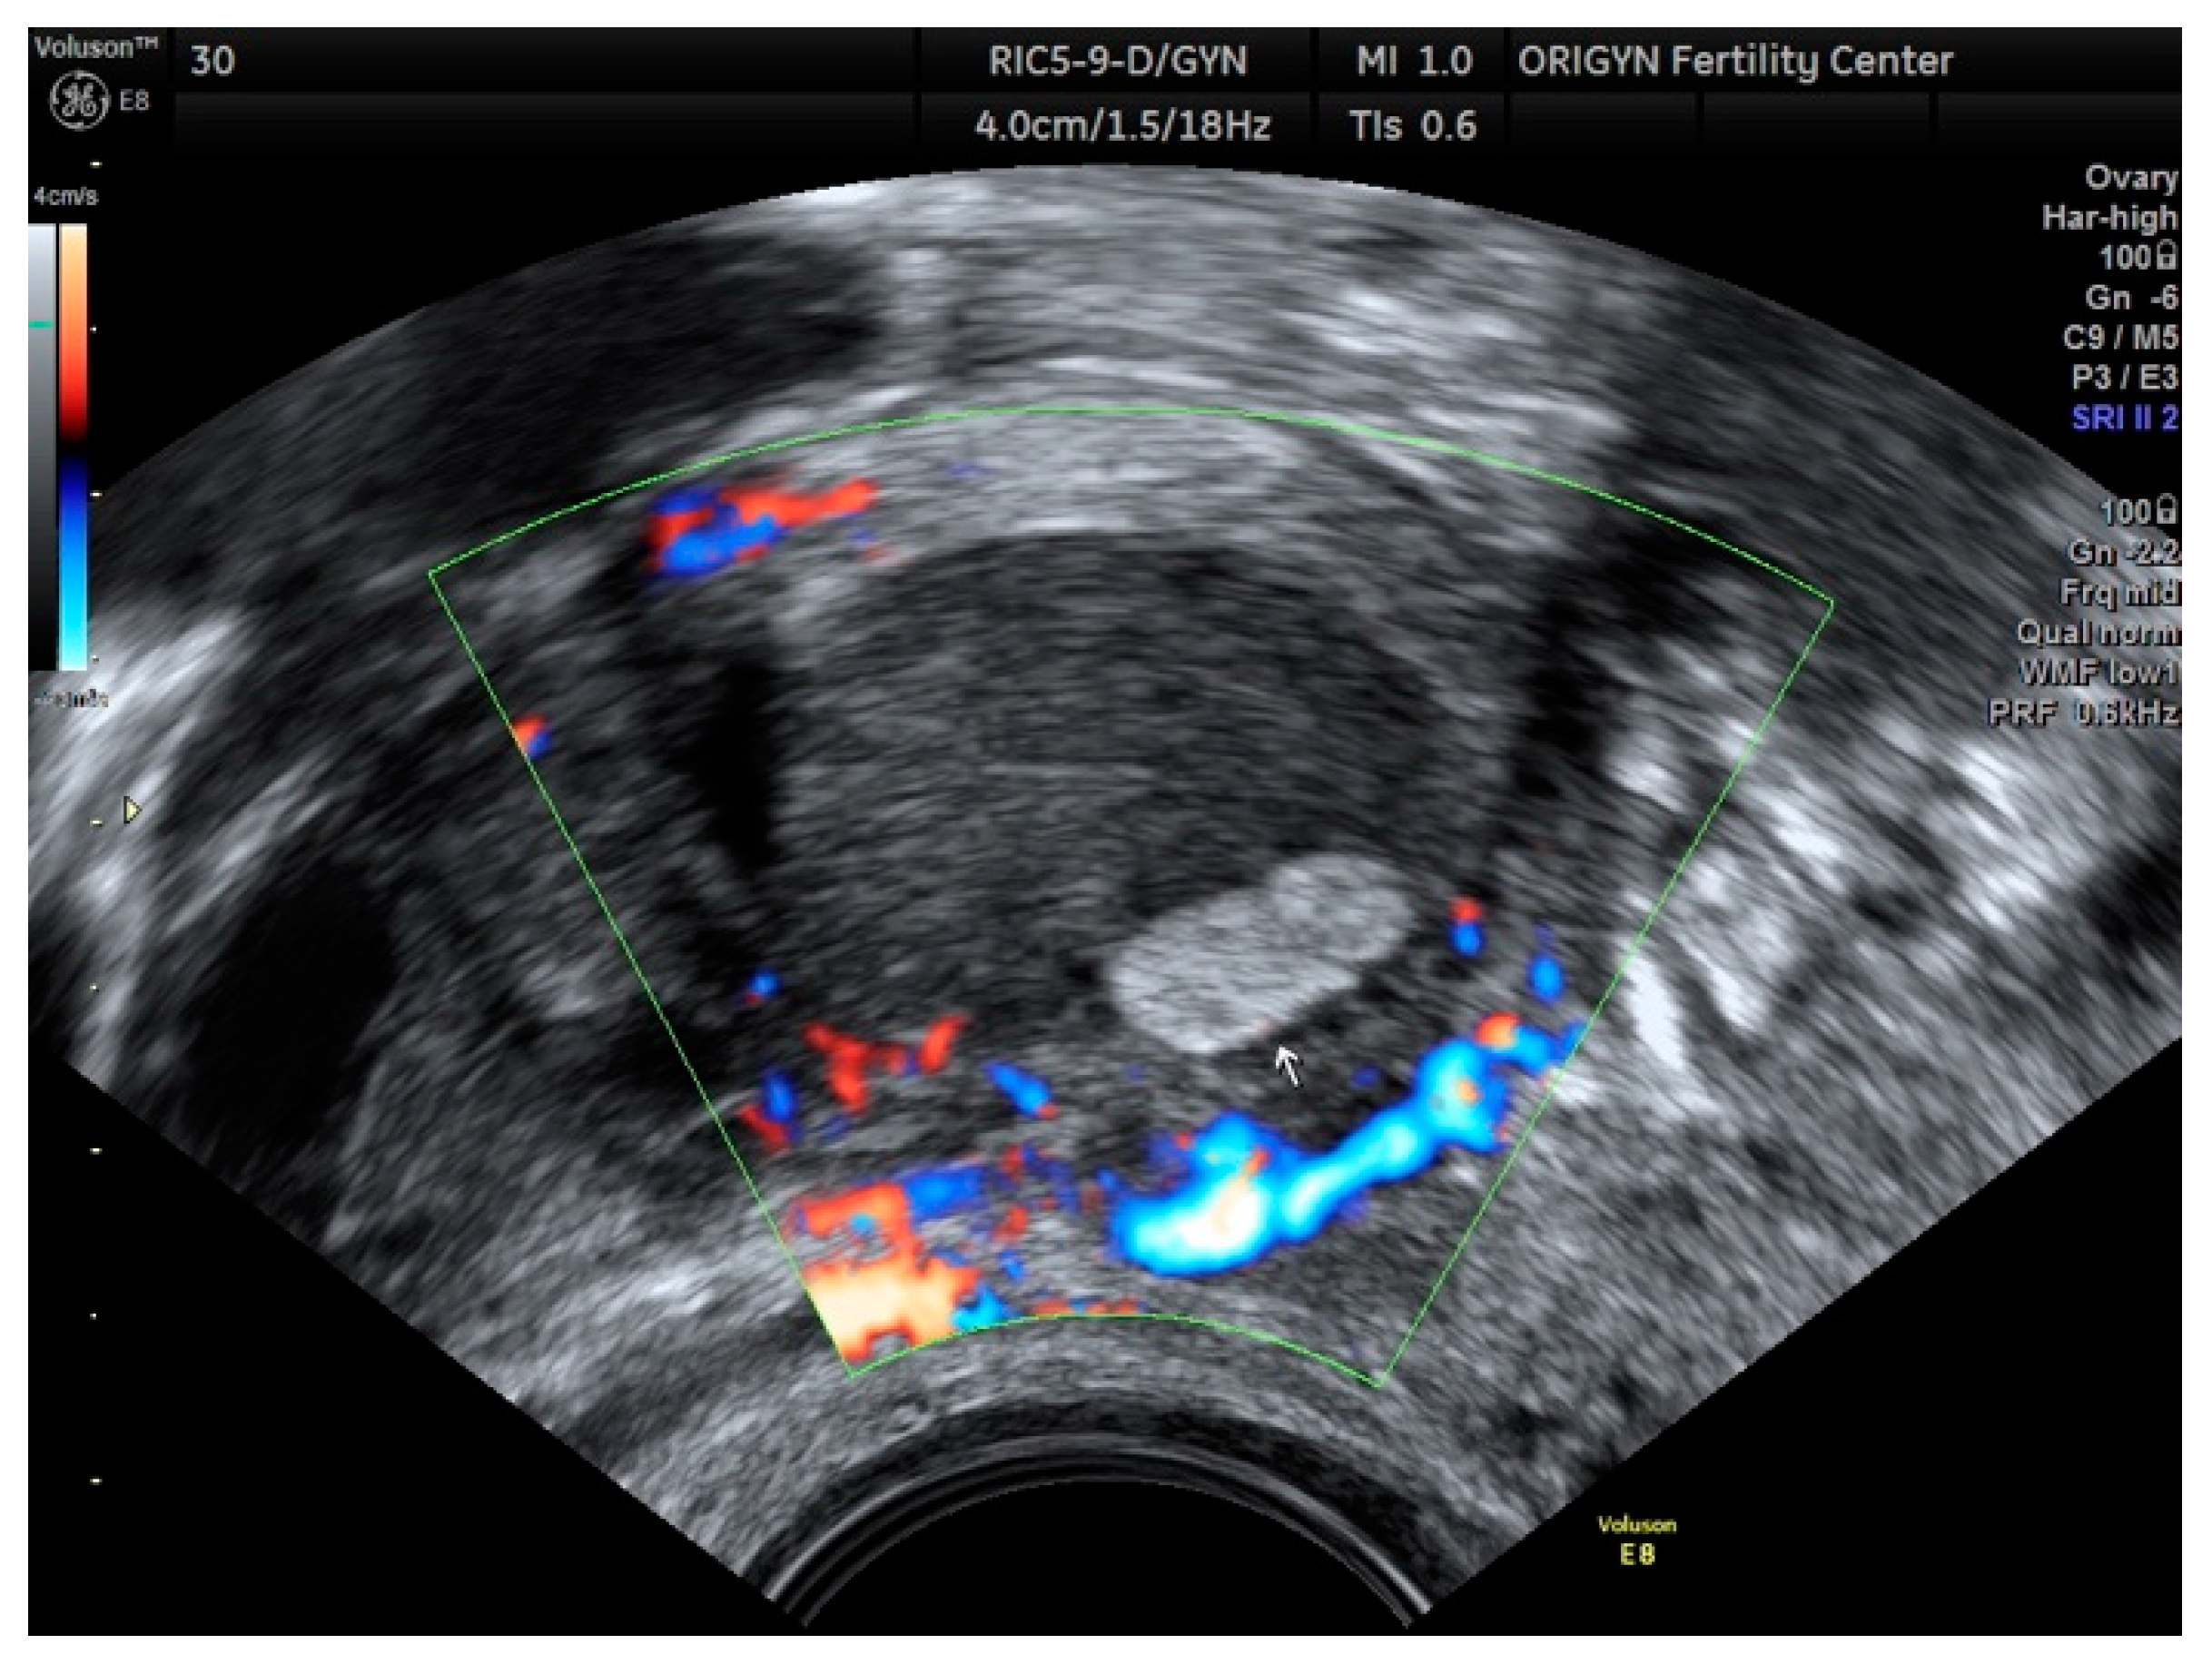

3.1. ADNEXA